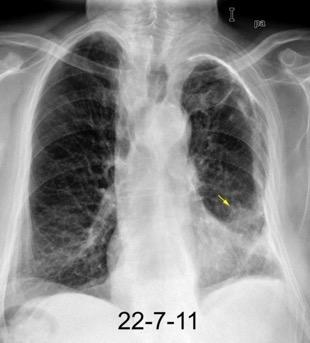

Neumonía a neumococos base izda. con derrame que aumenta.

Broncograma en lateral y en US.

(36-66% en ingresados)

66 pacientes con

Tb pleural probada

Ocasionalmente nivel hidro-aéreo por fístula broncopleural Consolidación........3% Ganglios……….....39%

Derrame...................65-98.5%

Lesiones pleurales. ........38 %

Afect. cisura interlobar….9%

Pl. mediastínica........... 1.5%

Afect. pulmonar 26/66 … 39%

Cambios fibróticos..........17%

Cavitación ......................12%

Nódulos heterogéneos.....6%